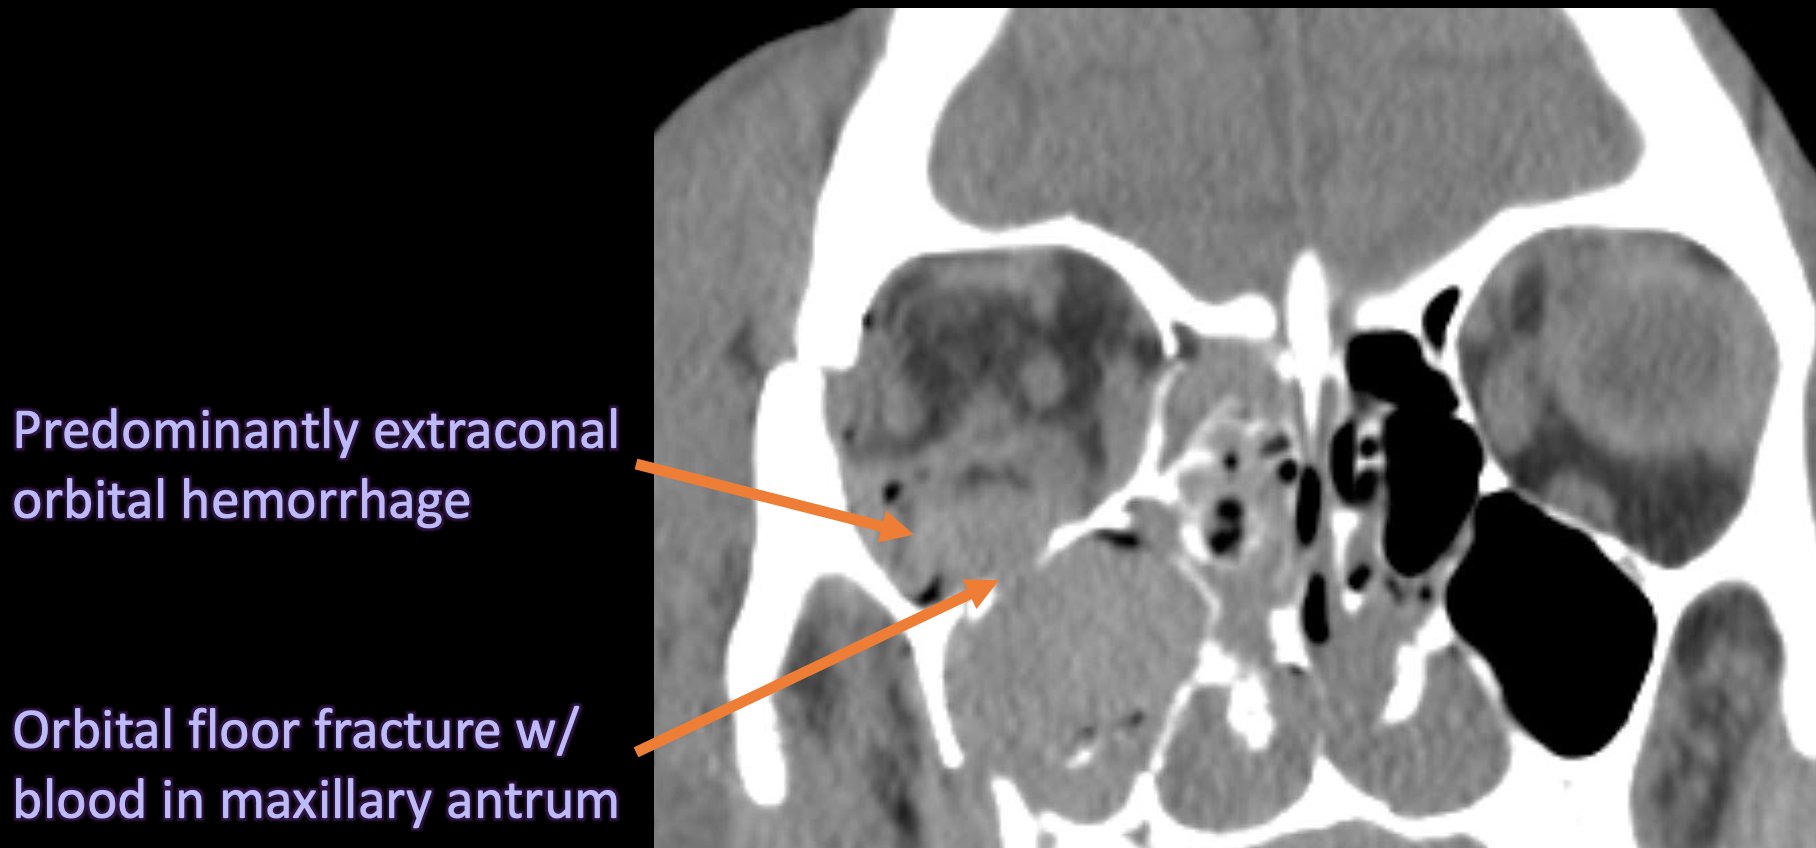

Orbital compartment syndrome. Coronal CT image in the bone window (a What Is Orbital Compartment Syndrome When intraorbital tension rises, damage to. Orbital compartment syndrome (ocs) is a true ophthalmological emergency. Orbital compartment syndrome is an uncommon, ophthalmic surgical emergency characterized by an acute rise in orbital pressure. It develops as a result of an acute rise in intra. Orbital compartment syndrome (ocs) is an emergent condition that occurs when intraorbital pressure exceeds ophthalmic artery pressure,. What Is Orbital Compartment Syndrome.